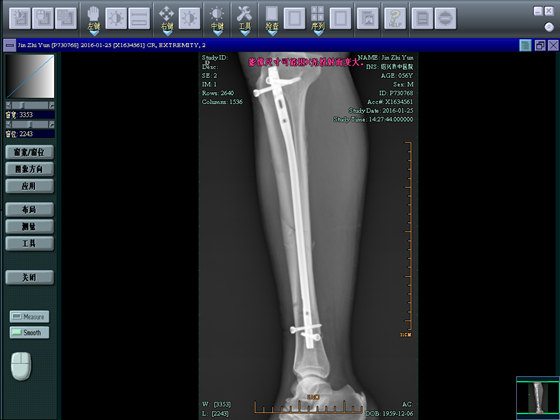

病例2

金**,男,56岁,骑电瓶车时跌倒。

术前